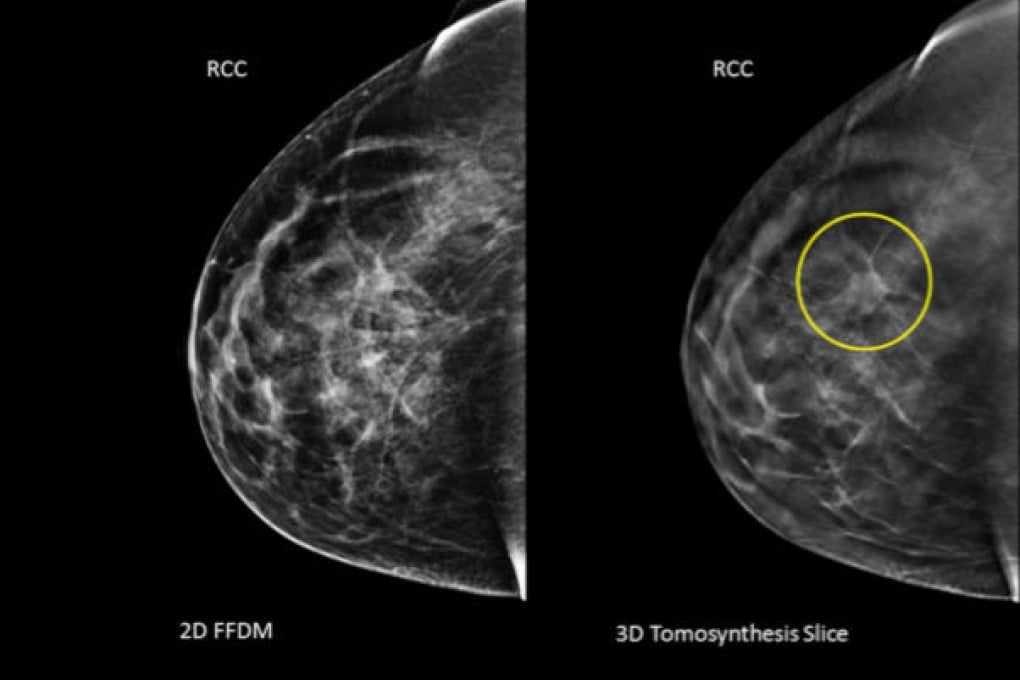

The technology, approved by the United States Food and Drug Administration in 2011, provides images that appear as slices of the breast, removing the effect of overlapping breast tissue that can obscure views of tumours.

The paper, published online in the Journal of the American Medical Association, reviewed 454,850 examinations from 13 sites across the country, 281,187 conducted with digital mammography and 173,663 that provided the traditional mammogram and tomosynthesis. The improved technology found 41 per cent more invasive cancers (4.1 per thousand women screened versus 2.9 per thousand) and more cancers overall.